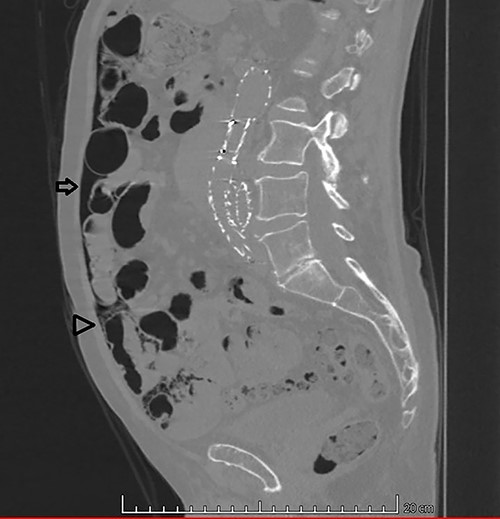

An 87-year-old male patient came to the radiology department to perform an abdominal computed tomography (CT) for follow-up of a bladder urothelial carcinoma. Upon CT evaluation, diffuse intestinal pneumatosis associated with pneumoperitoneum was identified on the exam (Fig. 1). The patient was called to return promptly to the hospital.

Sagittal CT image in lung window: (arrow) pneumoperitoneum and (arrow head) ‘bubbles’ within the walls of small intestine segment and the adjacent mesentery, featuring pneumatosis cystoides intestinalis and mesenteric.